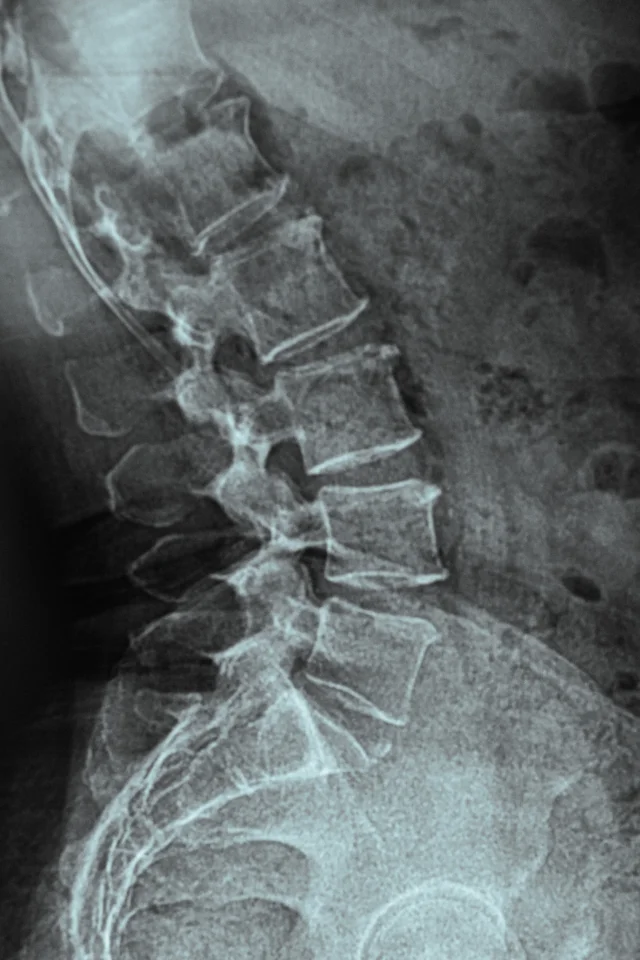

At iMsk & Spine Group, we understand that spine pain doesn’t just affect your back — it affects your whole life. That’s why we begin with a careful consultation and full spine evaluation to uncover the root cause of your discomfort. Whether it’s a herniated disc, degenerative changes, nerve compression, or spinal instability, our team develops a personalized treatment plan that prioritizes long-term comfort, mobility, and quality of life.

Using advanced diagnostics, decades of clinical experience, and a compassionate, patient-first approach, we treat a wide range of spinal disorders. Our goal isn’t just to relieve symptoms — it’s to help you regain strength, mobility, and vitality. Below are many of the common spinal disorders we treat.